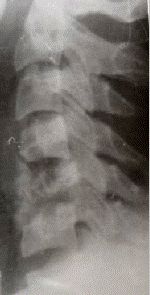

В качестве иллюстрации приводим рентгенологическую картину формирования костного блока у больного В., 21 лет, которому выполнен спондилодез на двух уровнях по поводу нестабильного перелома С6

позвонка (см. рисунок 1).

а) б) в)

Рис.1. Больной В., 21 лет. Д–з: нестабильный перелом тела С6

позвонка.

а – при поступлении; б – 7 дней после операции; в – 11 недель после операции.